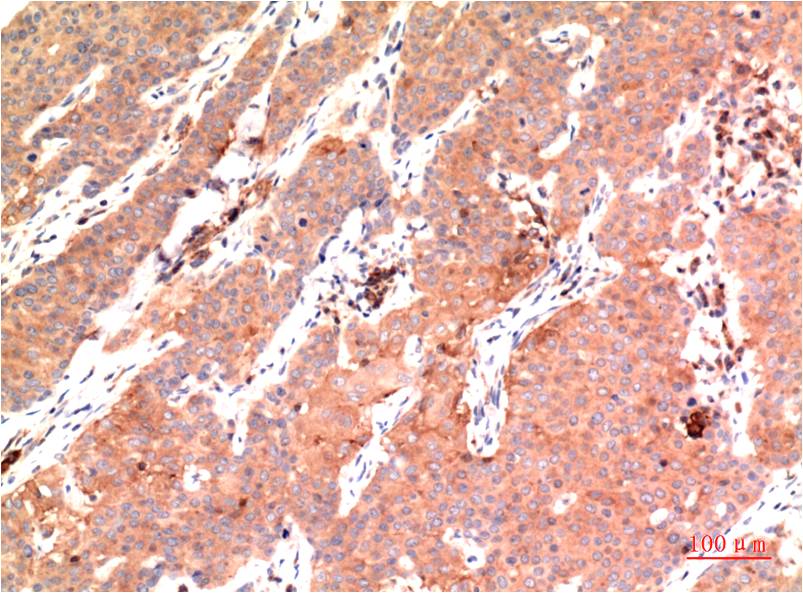

Immunohistochemical analysis of paraffin-embedded Human Colon Carcinoma Tissue using?Epsilon Tubulin(EM1311)Mouse mAb diluted at1:200.

Immunohistochemical analysis of paraffin-embedded Human Breast Carcinoma Tissue using?Epsilon Tubulin(EM1311 )Mouse mAb diluted at 1:200.